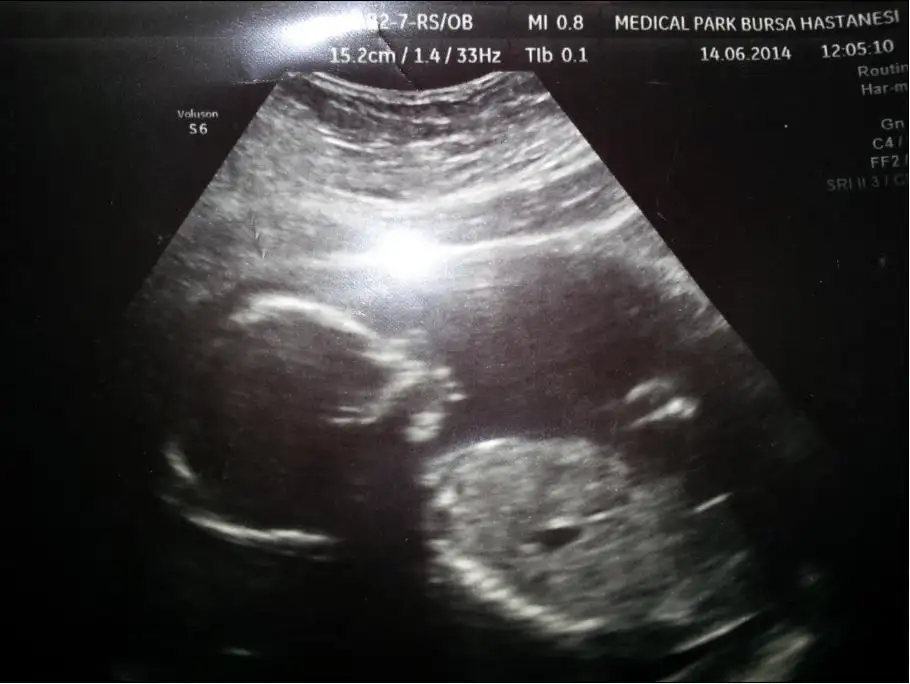

Canım maşallah bebişine ayağımı o yukarıda duran harekli bebiş sanırımBu da benim minik kızım, kolları sürekli yüzünün yanında olduğundan poz yakalayamıyoruz. Doktorumuzun çok içine sinen bir fotoğraf olmadı ama yapacak birşey yok

Bu da benim minik kızım, kolları sürekli yüzünün yanında olduğundan poz yakalayamıyoruz. Doktorumuzun çok içine sinen bir fotoğraf olmadı ama yapacak birşey yok

Hareketinden dolayı öyle çıkmıştır annesi burnuna laf etmeyin bebişin hem şişlikte vardır onda şimdiilk zamanlarından beri çok hareketli zaten, onun hareket etmesi yüzünden çok geç öğrenebildik cinsiyetini. Şimdide aynen devam, ne gece duruyor ne gündüz, bu seferde poz yakalayamıyoruz. Yakalasakta böyle çıkıyor. Annem gördü, "ee bunun hokka gibi burnu vardı, karadenizli burnu olmuş " dediAslında resimdekiyle ilgisi yok burnunun. O görünen de kolu ve kordon bağı